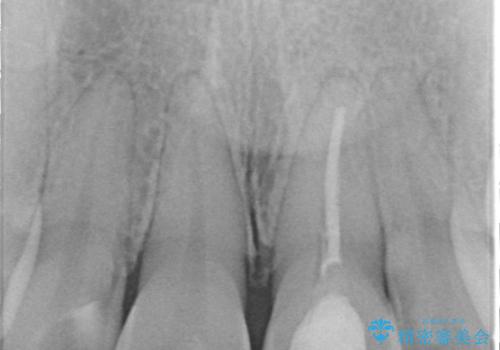

- 「以前、他院で神経を取った前歯がだんだん黒ずんできた」という見た目の改善を主訴にご来院されました。 診査の結果、神経を取り除いた後の歯(失活歯)特有の変色が起きており、さらに根の先端にわずかな影が見られたため、内部で感染が起きている可能性がありました。

精密な再根管治療: 古い充填材を除去し、歯科用顕微鏡を用いて根管内を徹底的に清掃・殺菌しました。根の先まで確実に薬剤を詰め直すことで、将来的な根尖病変(根の先の膿)のリスクを最小限に抑えました。